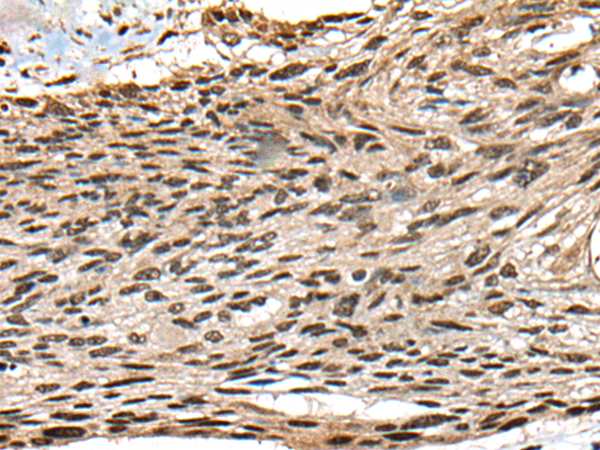

分类: 科研抗体货号: P09447别名: JM11应用: IHC反应种属: Human, Mouse